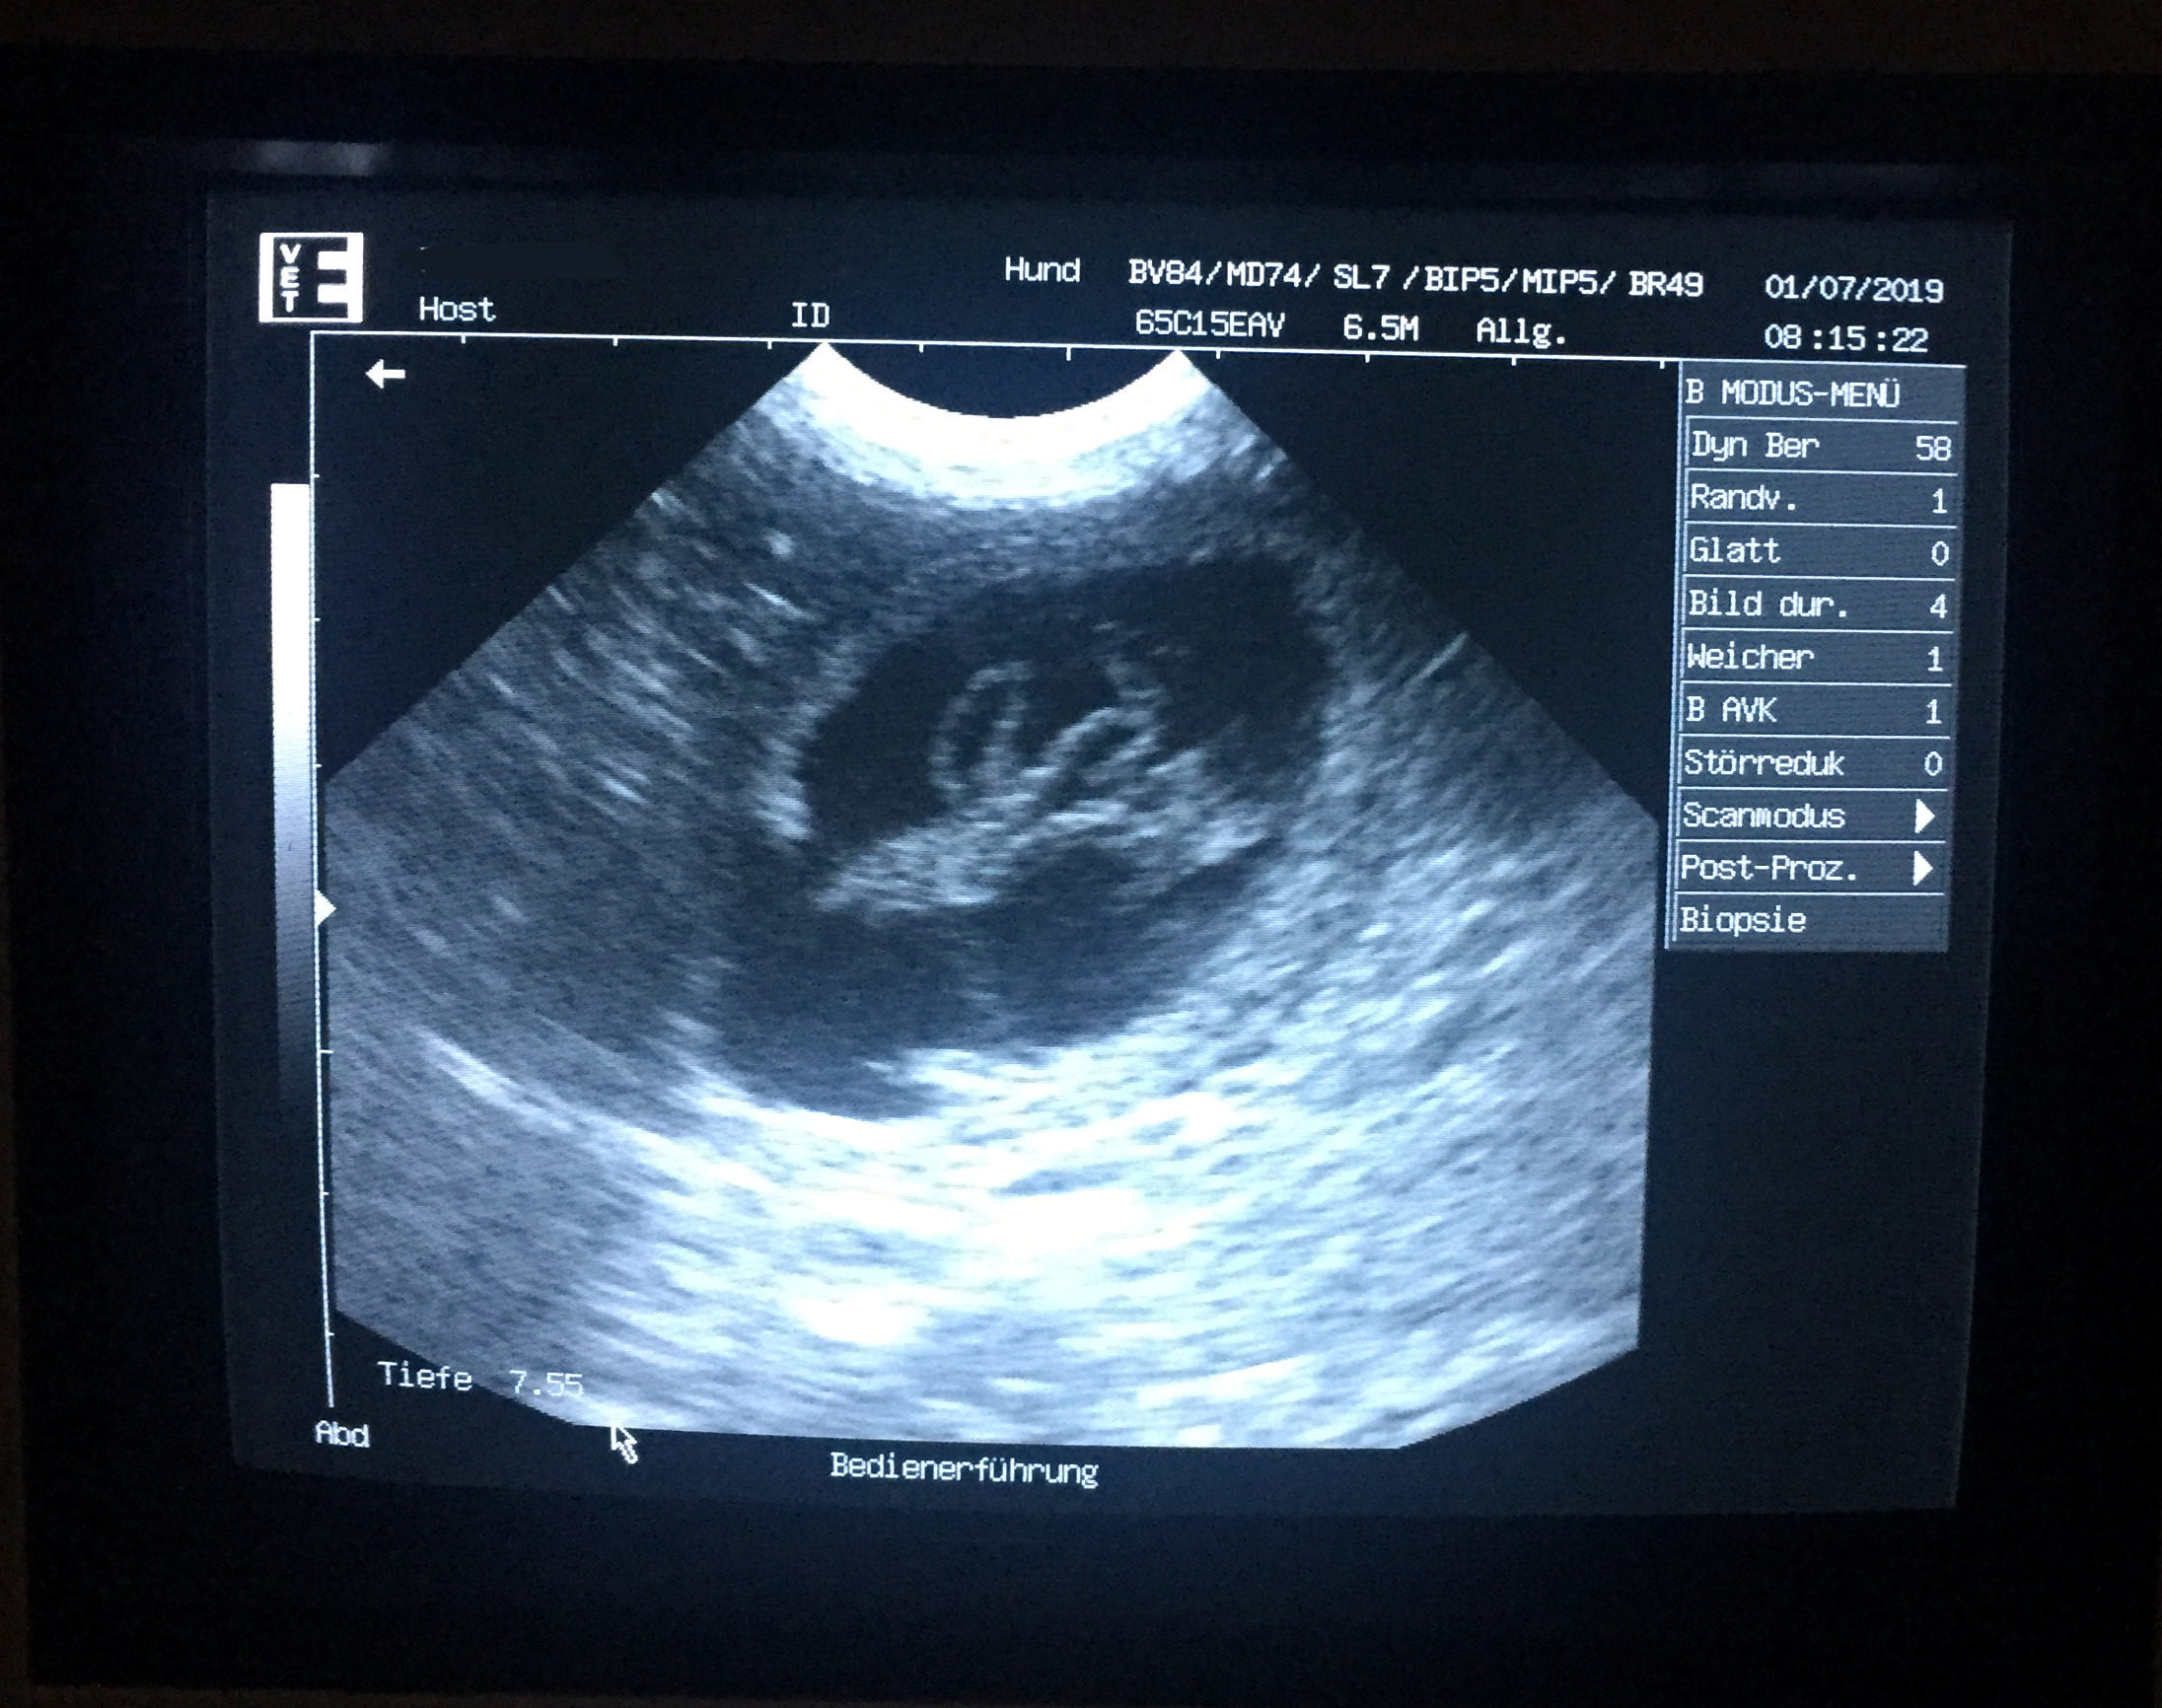

Nach der Bestätigung der Trächtigkeit durch eine Ultraschalluntersuchung erwarten wir auf dem Brunnenfeld um den 1.August herum unsere I-Wurfwelpen.